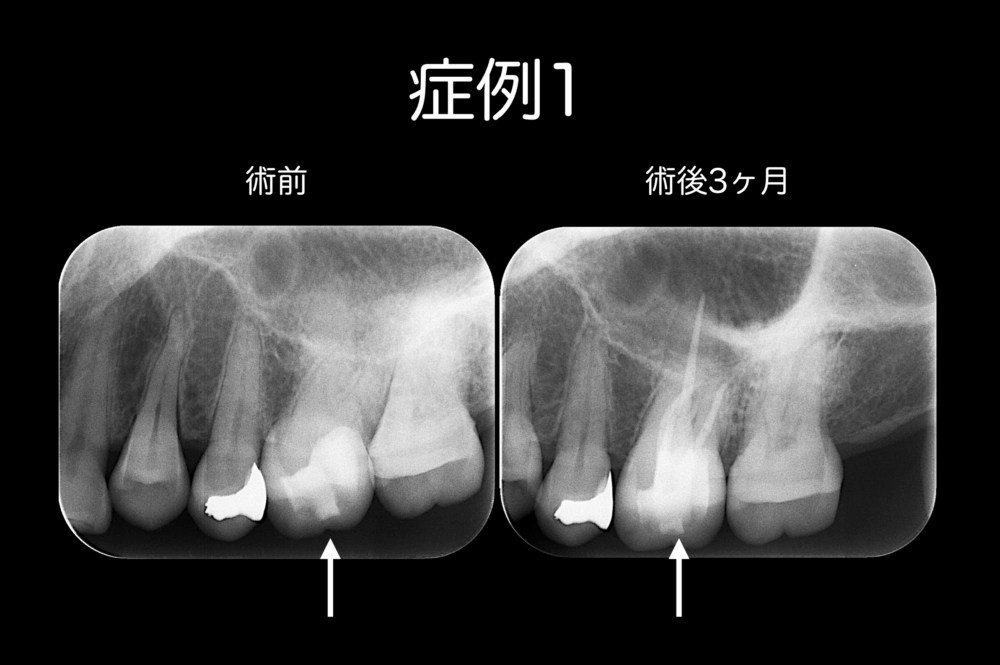

症例1の患者さんは、50歳女性です。

定期的に冷たいものに痛みを感じる、とのことでももこ歯科を受診されました。

原因歯は左上顎第一大臼歯(白い矢印)で根管治療を行い、直接法でファイバーポストを築造しました。根管充填も築造体も隙間なく詰められています。